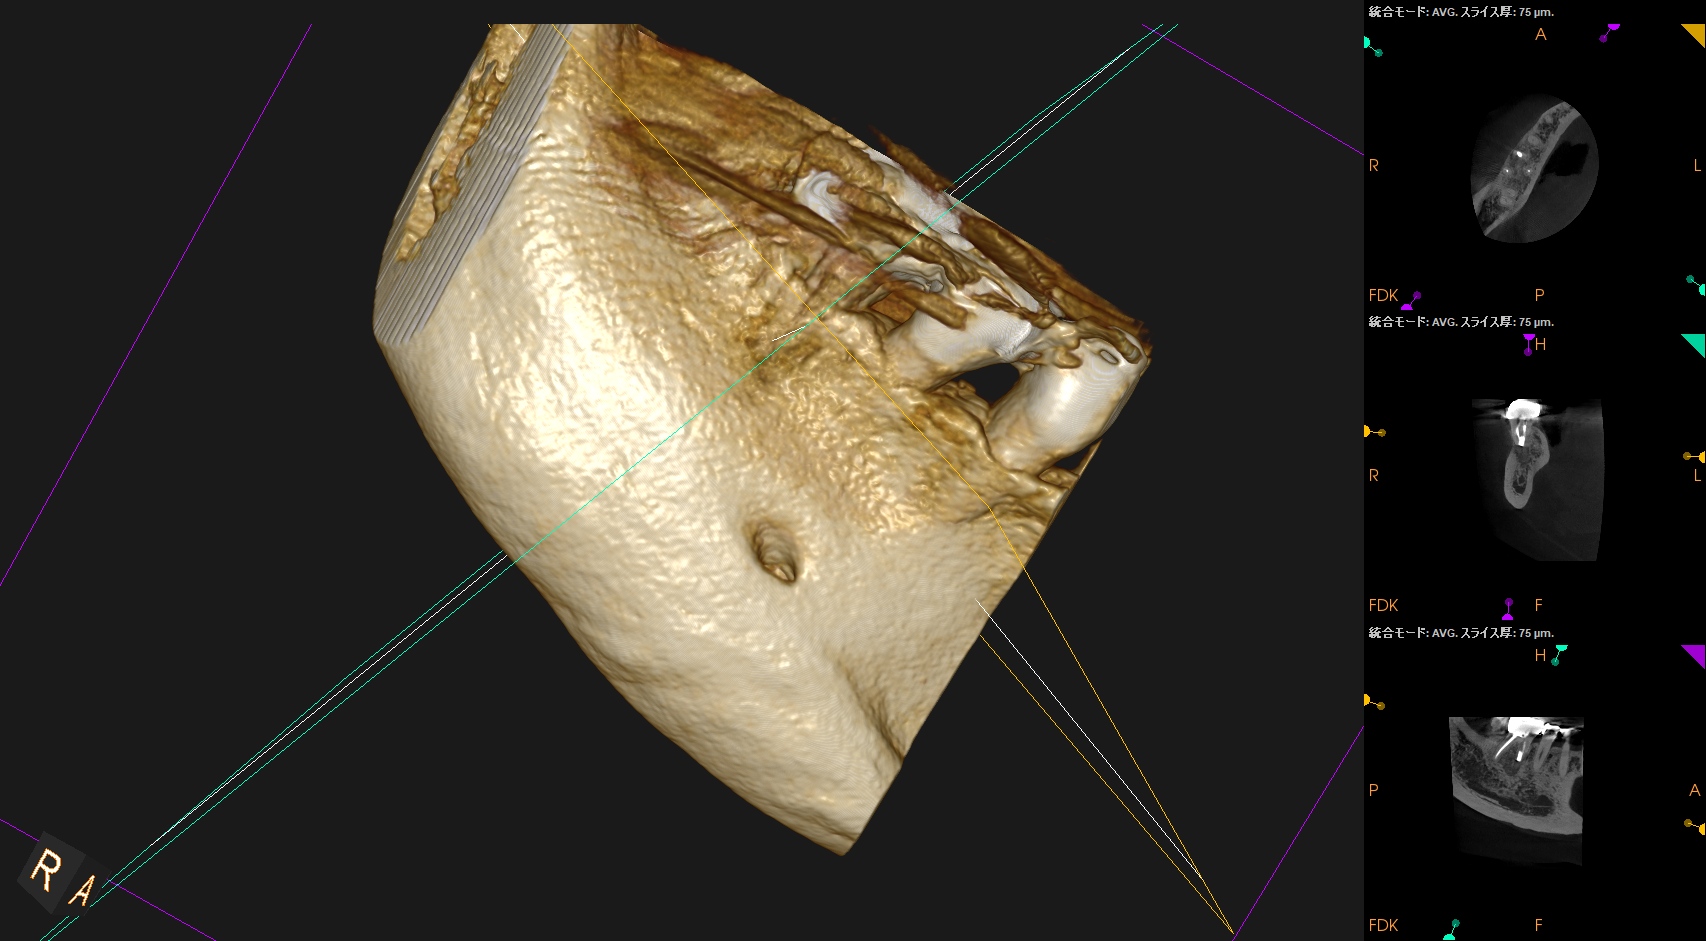

#30 M Apicoectomy 6M recall(2026.2.18)

大幅に問題が改善している。

初診時と比較した。

歯槽骨が劇的に再生している。

臨床症状もない。